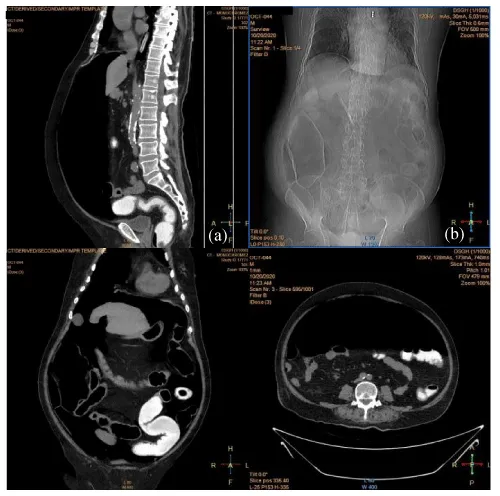

On Day 24 symptom onset, he had loose motion (2 to 3 times per day). There was no abdominal pain or vomiting. There was no blood or mucus in stool. Then he noticed abdominal distension gradually and discomfort. On Day 28 symptom onset, there was features of peritonism on examination. CT abdomen revealed massive free gas and oedematous colon on right side (Figure 2). Later, he developed fever and blood pressure dropped. Inotropes, metronidazole and fluid and electrolytes were given.